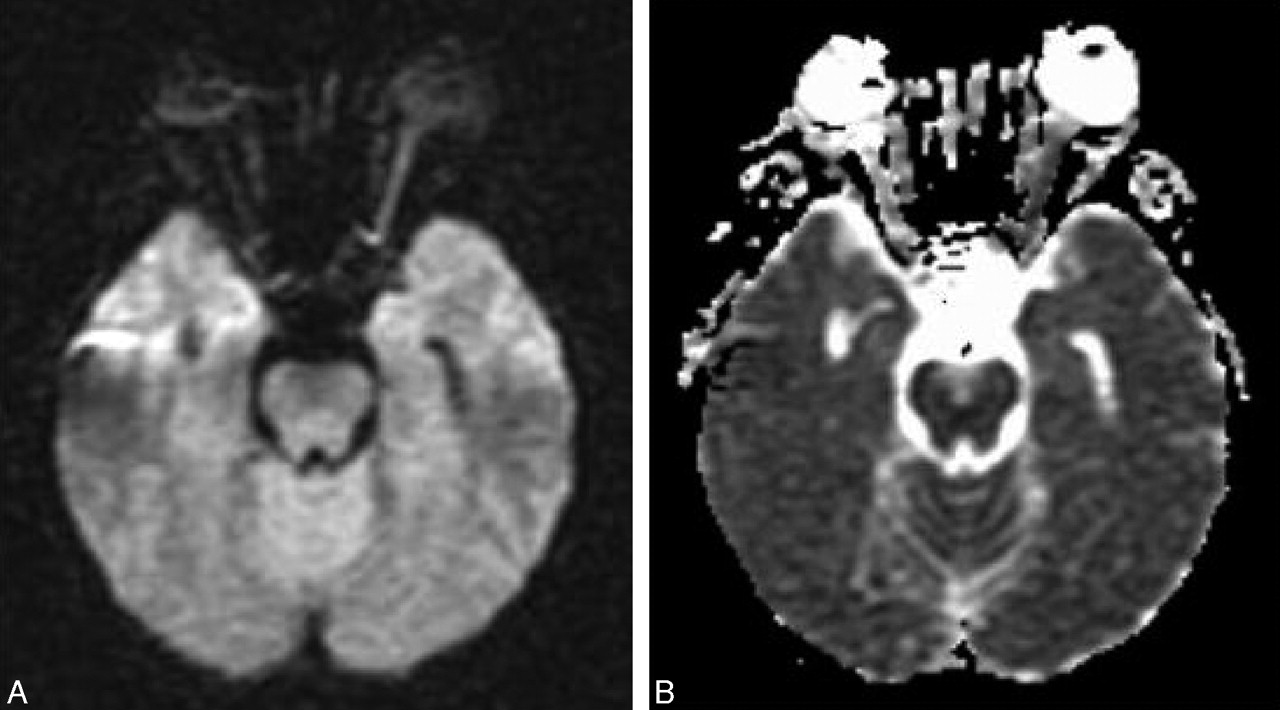

MR imaging of the brain preformed on day 2 after admission showed high signal intensity in the left optic nerve on diffusion imaging (Fig 1A) with decreased apparent diffusion coefficient (ADC; Fig 1B) indicating ischemic injury. Diffusion-weighted imaging (DWI) parameters were axial plane, TR = 10,000, TE = 94, b = 1000, section thickness = 5 mm with 0.5-mm gap, matrix = 128 × 128, field of view = 30 cm, standard quadrature head coil, and 1.5T Echospeed MR imaging (GE Healthcare, Milwaukee, Wis). ADC in the left optic nerve was decreased by 46% compared with the right optic nerve. Fluid-attenuated inversion recovery images of the brain revealed a few small foci of increased T2 signal in the hemispheric white matter, which indicated the presence of mild microangiopathic disease.

A, Diffusion-weighted image (TR, 10 seconds; TE, 94.5 milliseconds; b, 1000 s/mm2) shows much higher signal intensity in the left optic nerve compared with the right. B, ADC image shows decreased signal intensity in the left optic nerve proving that the higher signal intensity in the left optic nerve on DWI is due to restriction in water diffusion.